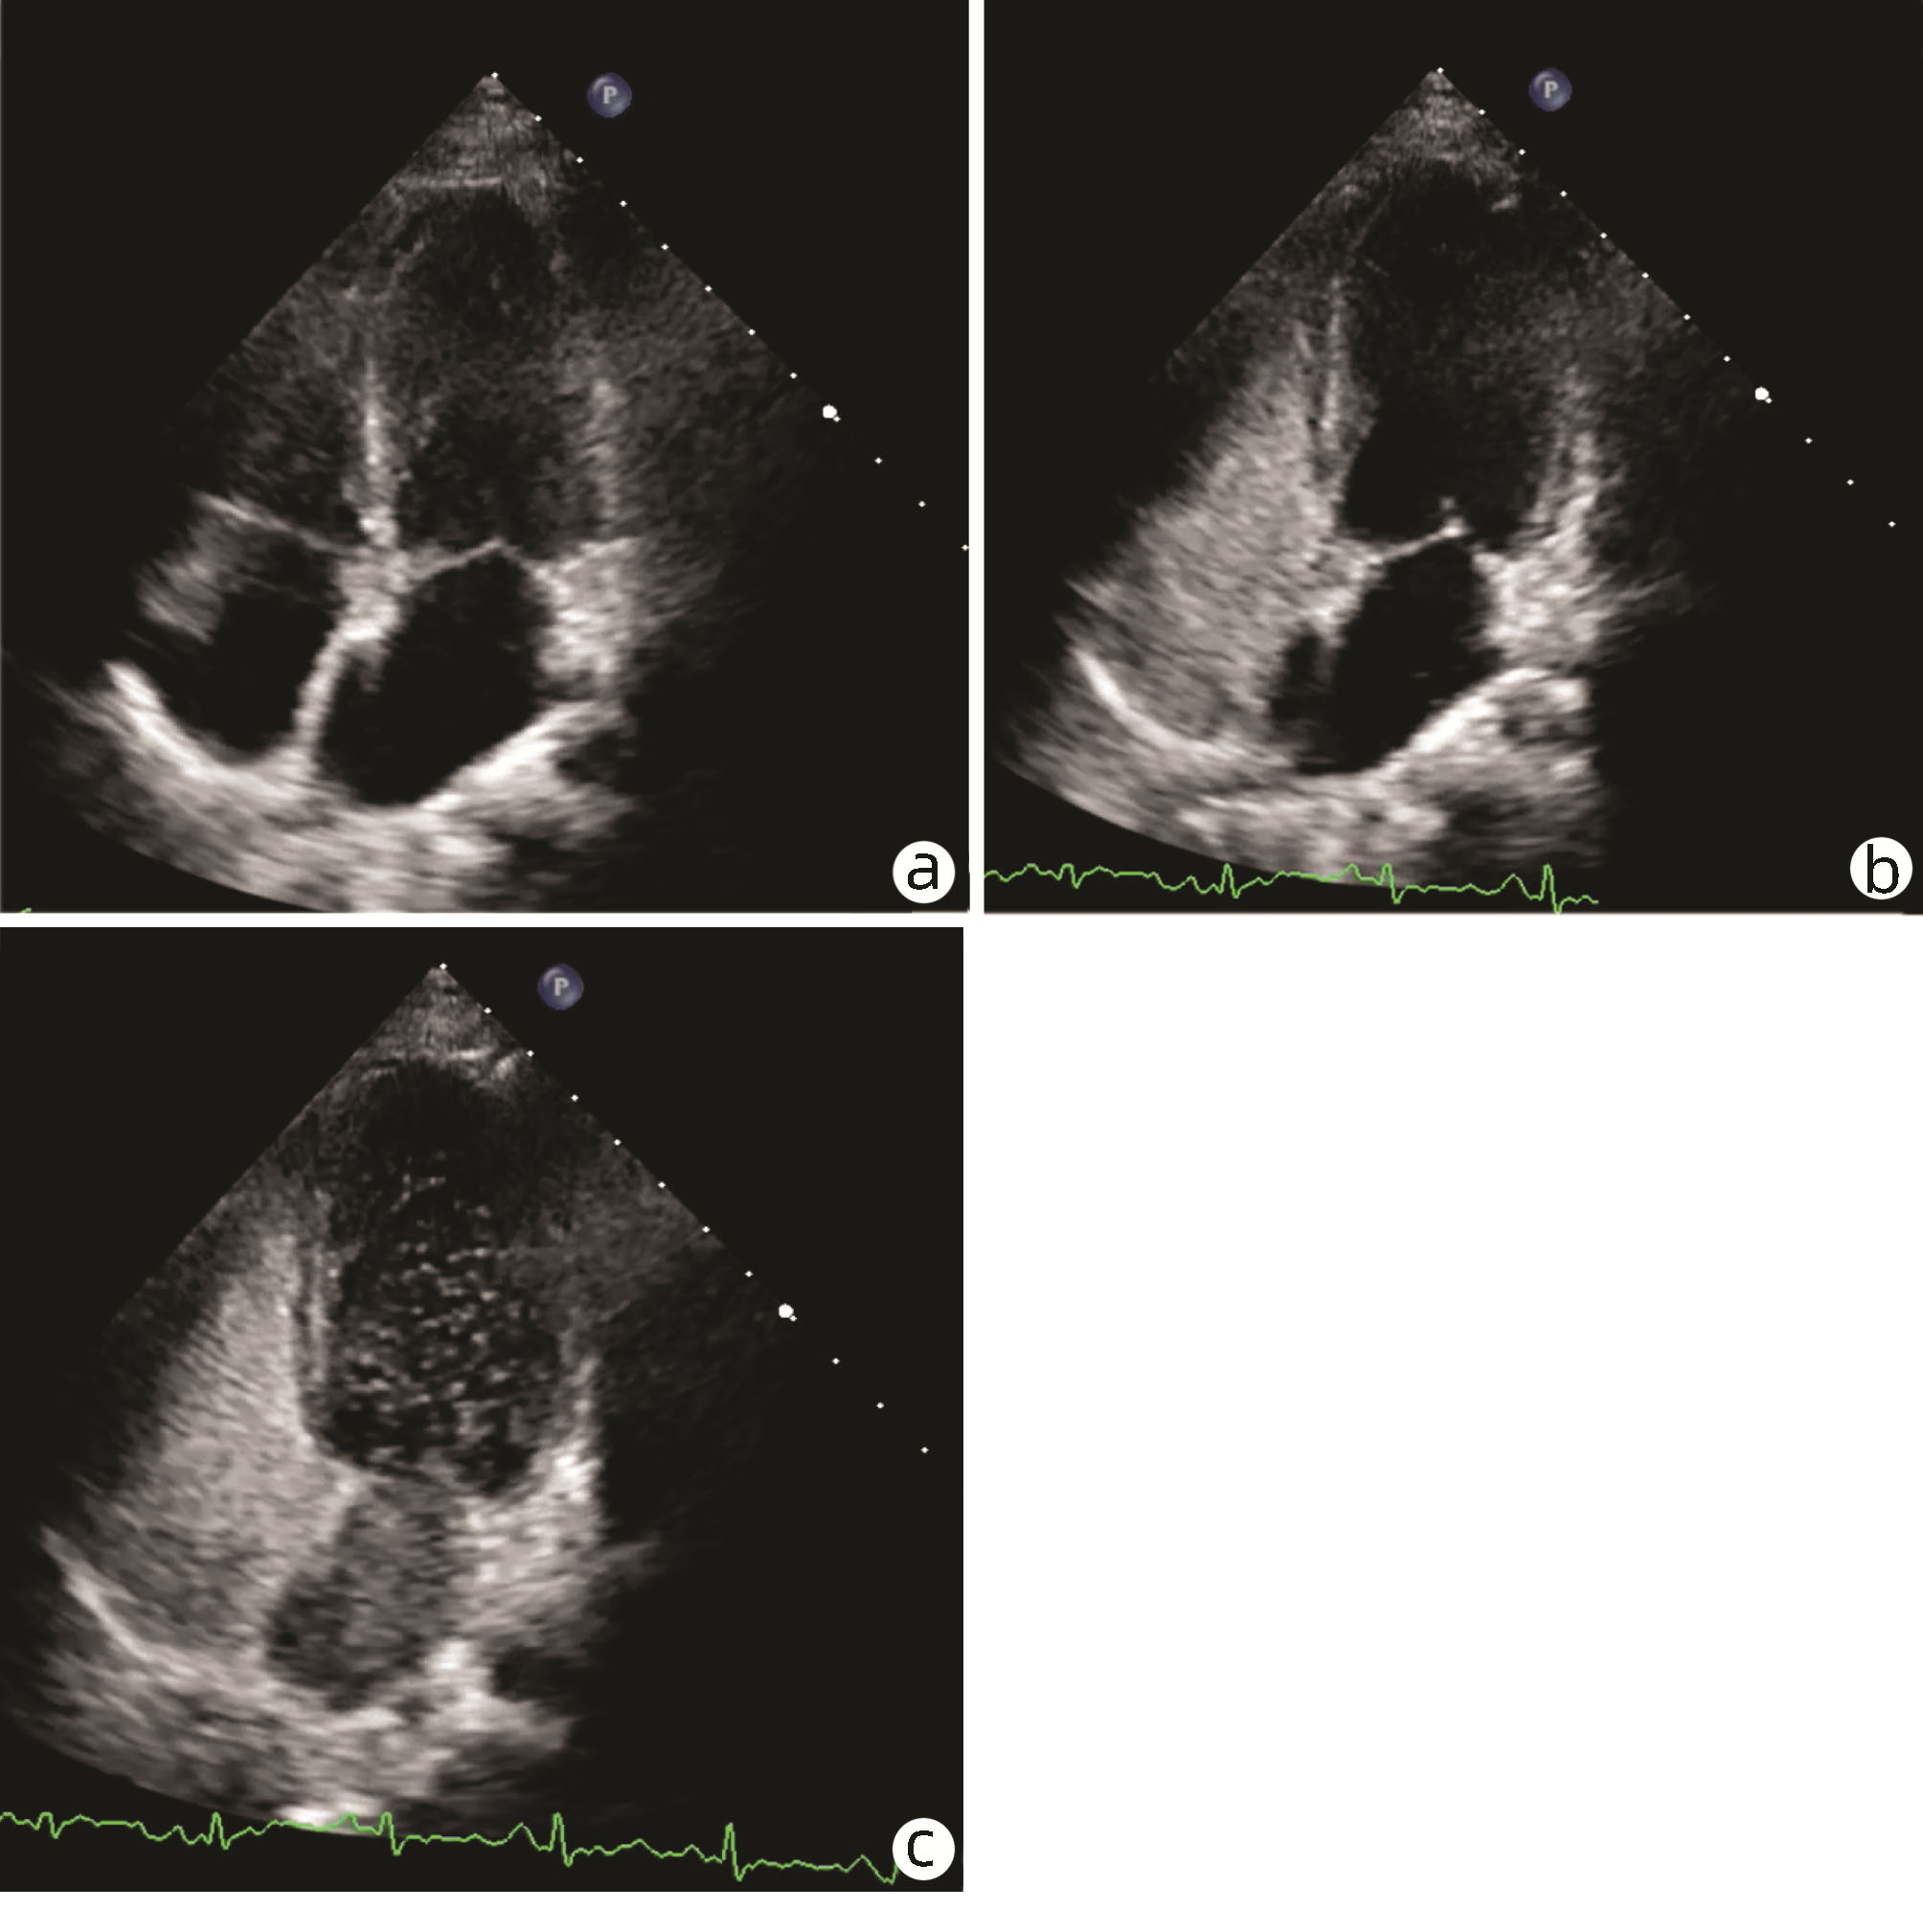

Hepatopulmonary syndrome after craniopharyngioma operation in children: A case report

Tingting DU, Hui YAO, Yakun LI, Xiaoli HUANG, Jie LUO

2022, 38(7): 1620-1625. DOI: 10.3969/j.issn.1001-5256.2022.07.030

Abstract(1022) HTML (325) PDF (2776KB)(75)

Abstract: